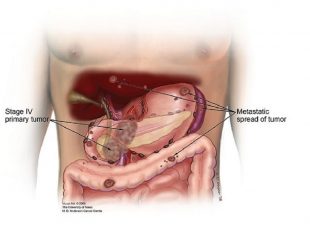

مرحله 4 سرطان لوزالمعده یا پانکراس

لوزالمعده اندامی است که به تسهیل عملکرد دستگاه گوارش و تنظیم قند خون کمک می کند. هنگامی که سرطان از ...